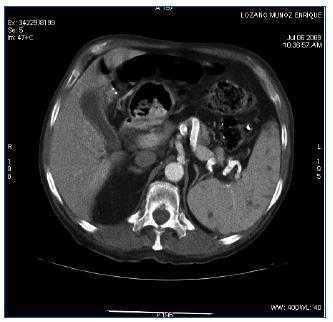

La evolución posterior del paciente es favorable, con desaparición de la fiebre, mejoría del estado general y aumento de peso que permite incluso la rehabilitación y deambulación. A los 2 meses de iniciado el tratamiento se realiza TAC de control en la que se aprecian una importante reducción del tamaño y del número de las adenopatías mediastínicas, una disminución del número de adenopatías paratraqueales, un descenso del tamaño y de la densidad de la lesiones parenquimatosas en pulmón y la desaparición de las imágenes esplénicas, quedando únicamente una lesión hipodensa en el polo anterior del bazo de menor tamaño que en la TAC previa (figura 2).

Figura 2. TAC con contraste a nivel esplénico tras 2 meses de tratamiento con tuberculostáticos.